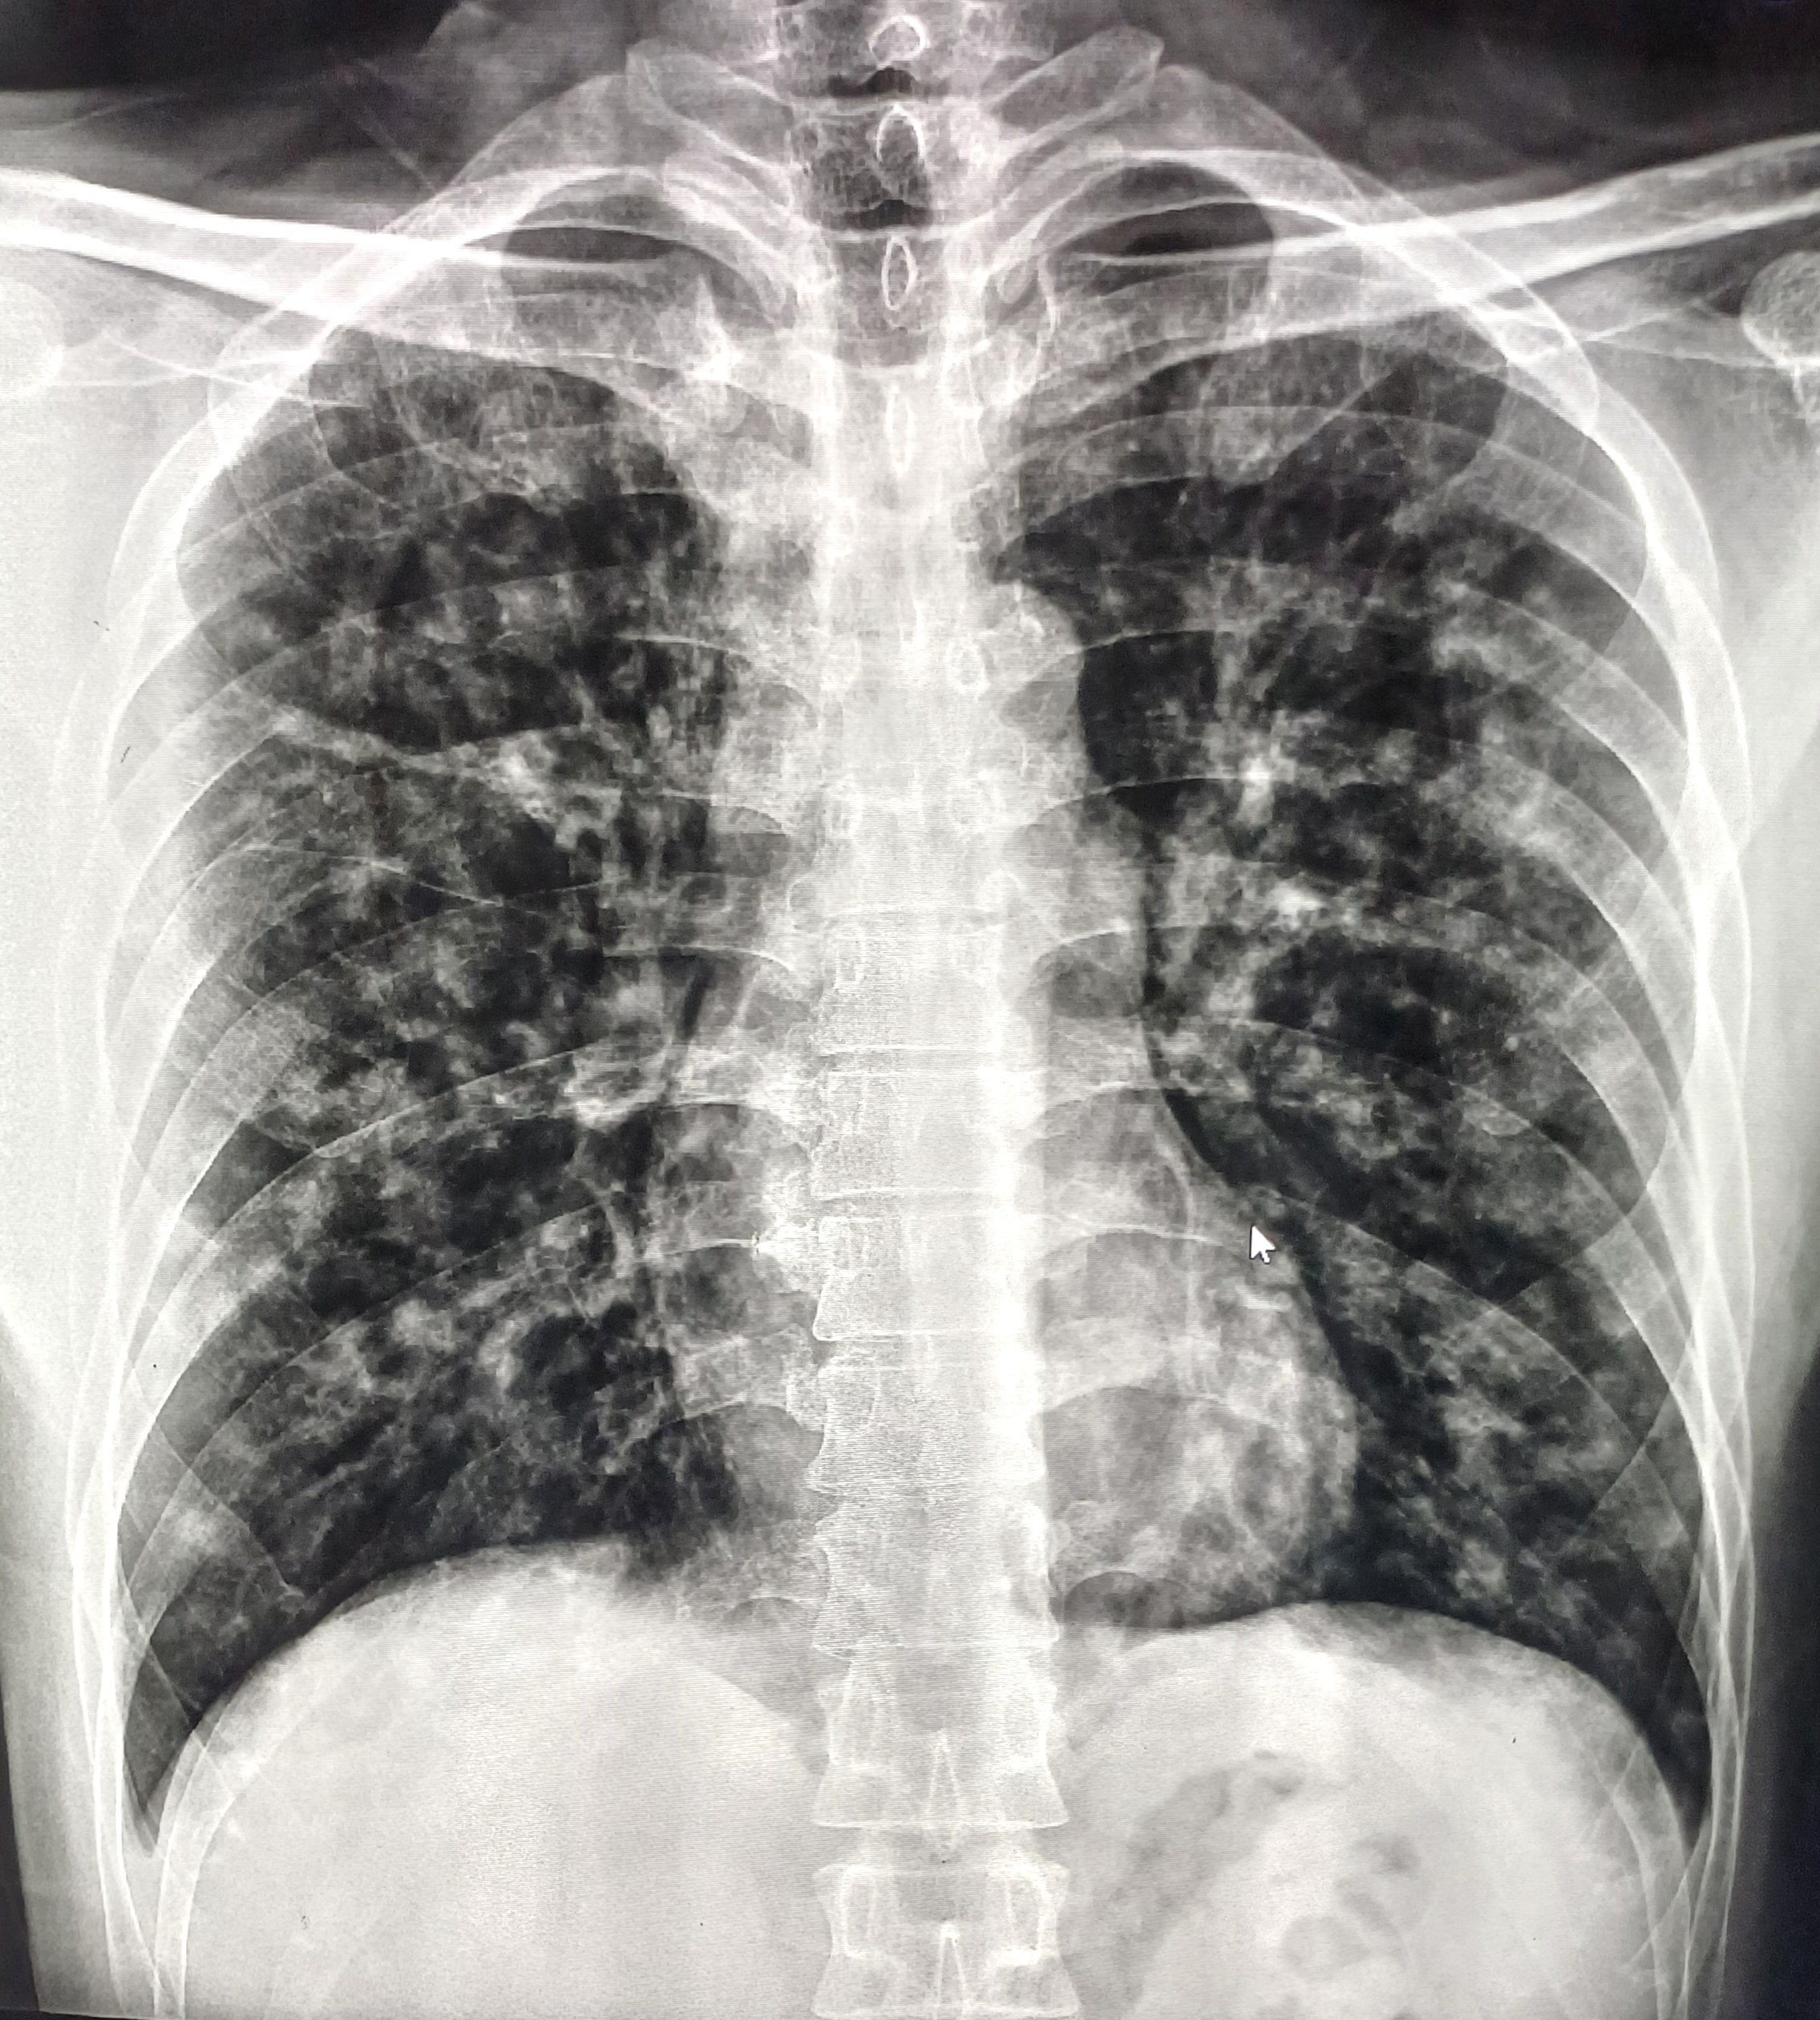

| 15 | IGGMC, Nagpur, Nagpur | P2 | 29-4457 | Tulsabai Atram | Consent taken on Paper | 64 Yrs. |

Provisional Diag : ?

Final Diag : ILD (Interstitial Lung Disease) |

Non-TB Case (Confirmed) | Multiple Ill-Defined nodular opacity noted bilateral zone likely fibrotic changes | Abnormality visible on x-ray |

View |

|||